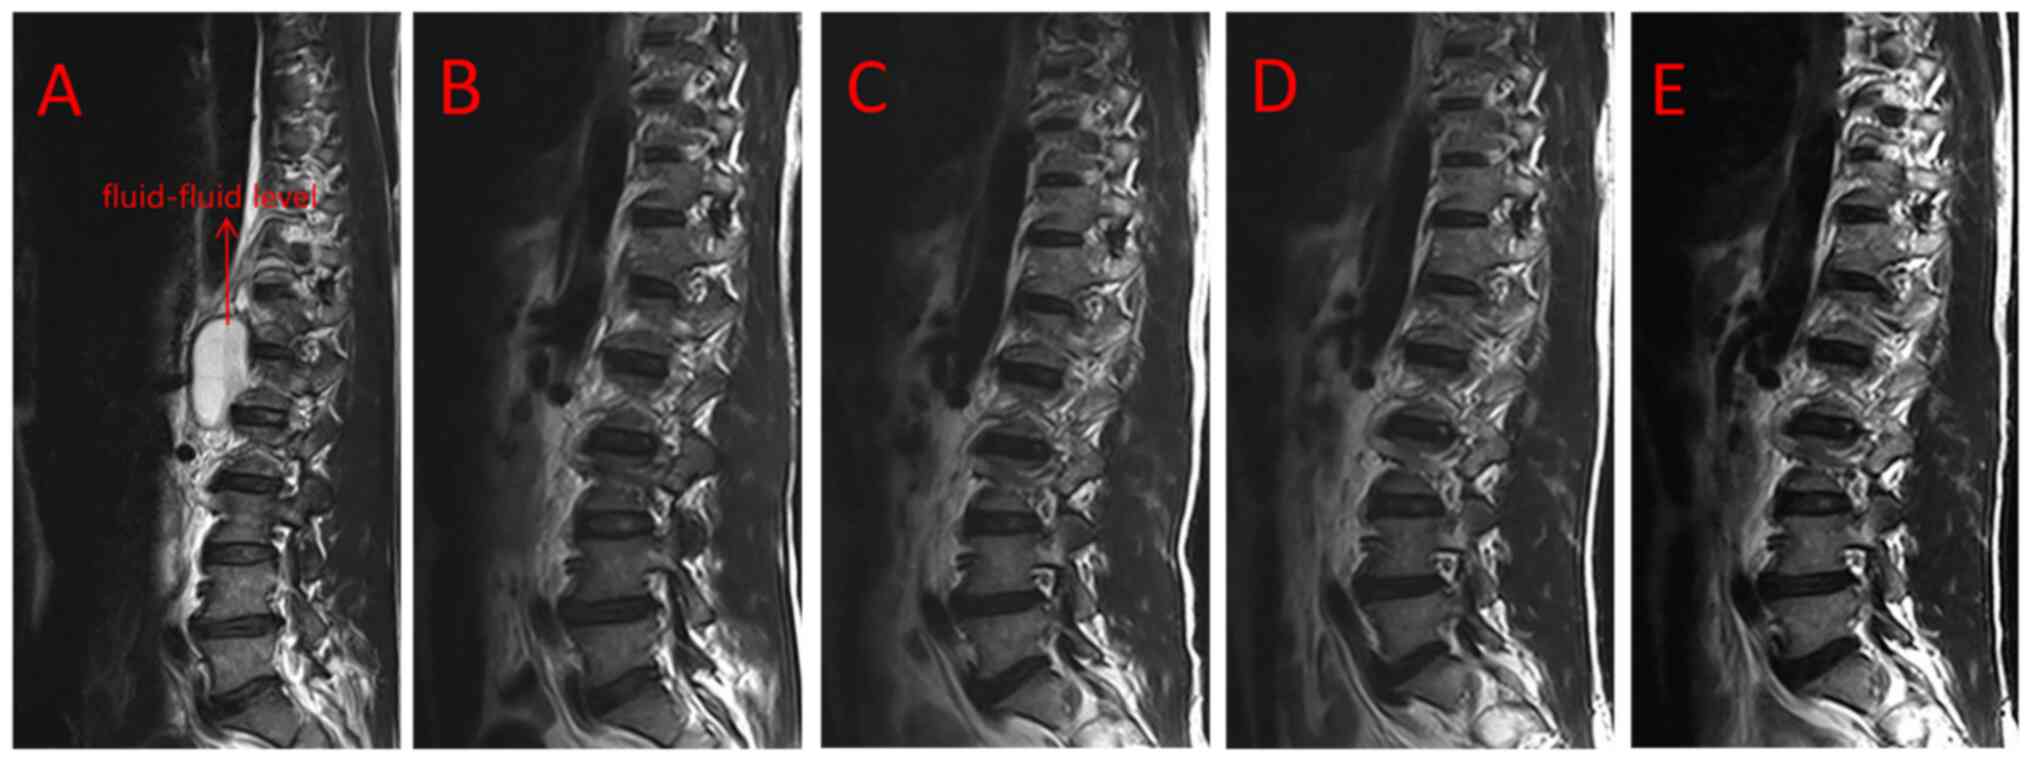

the patient markedly improved. Re-examination using MRI revealed

that the cyst had been completely removed. Of note, no recurrence

of the cyst and any clinical symptom was observed at the immediate,

3 months, 1 year and 3 years postoperatively (Fig. 4A-E).